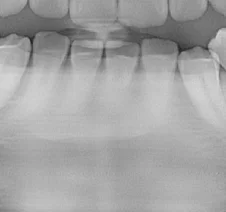

However, because this patient was scanned on a panoramic x-ray than can shift the focal trough, these apices can also be revealed. Again, this is done simply by using the data captured during the original scan – no additional scans are needed. You’ll notice that in this “layer”, the crowns are less visible. This is because the maxillary anteriors have dramatic angles to the emergence profiles and therefore the crowns are in a very different layer than the apices.